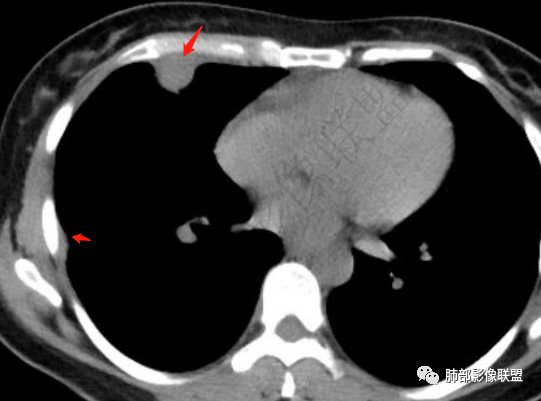

胸膜多个结节,附近胸壁脂肪间隙密度增高,提示有胸壁蔓延或侵犯。

1.胸膜多发结节,边缘比较光滑,累及胸壁(胸痛也符合,一年),表现为脂肪间隙密度增高,最大的病灶累及肺内,附近有渗出,但是无放射状表现,增强中央有坏死灶,一月后似有缩小,肋骨完整未见破坏,支持炎性可能大!